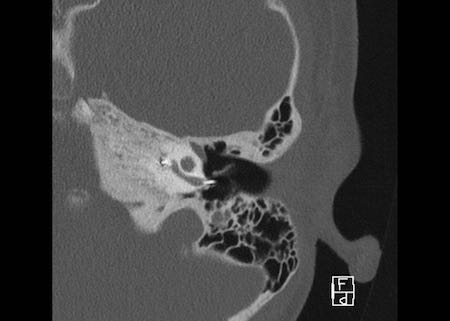

Bên trái là hình ảnh của một bé trai 10 tuổi, được lên kế hoạch cấy ốc tai điện tử.

Có sự giãn rộng và ngắn lại của ống bán khuyên ngoài.

Tiền đình tương đối lớn (mũi tên).